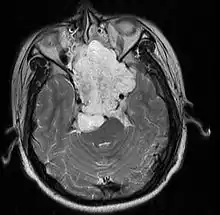

| MRI of extensive clival chordoma in 17-year-old male patient, axial view. Tumor in the nasopharynx extending from nasal cavity to brainstem posteriorly is clearly visible. | |

Chordomas can arise from bone in the skull base and anywhere along the spine. The two most common locations are cranially at the clivus and in the sacrum at the bottom of the spine.[2]